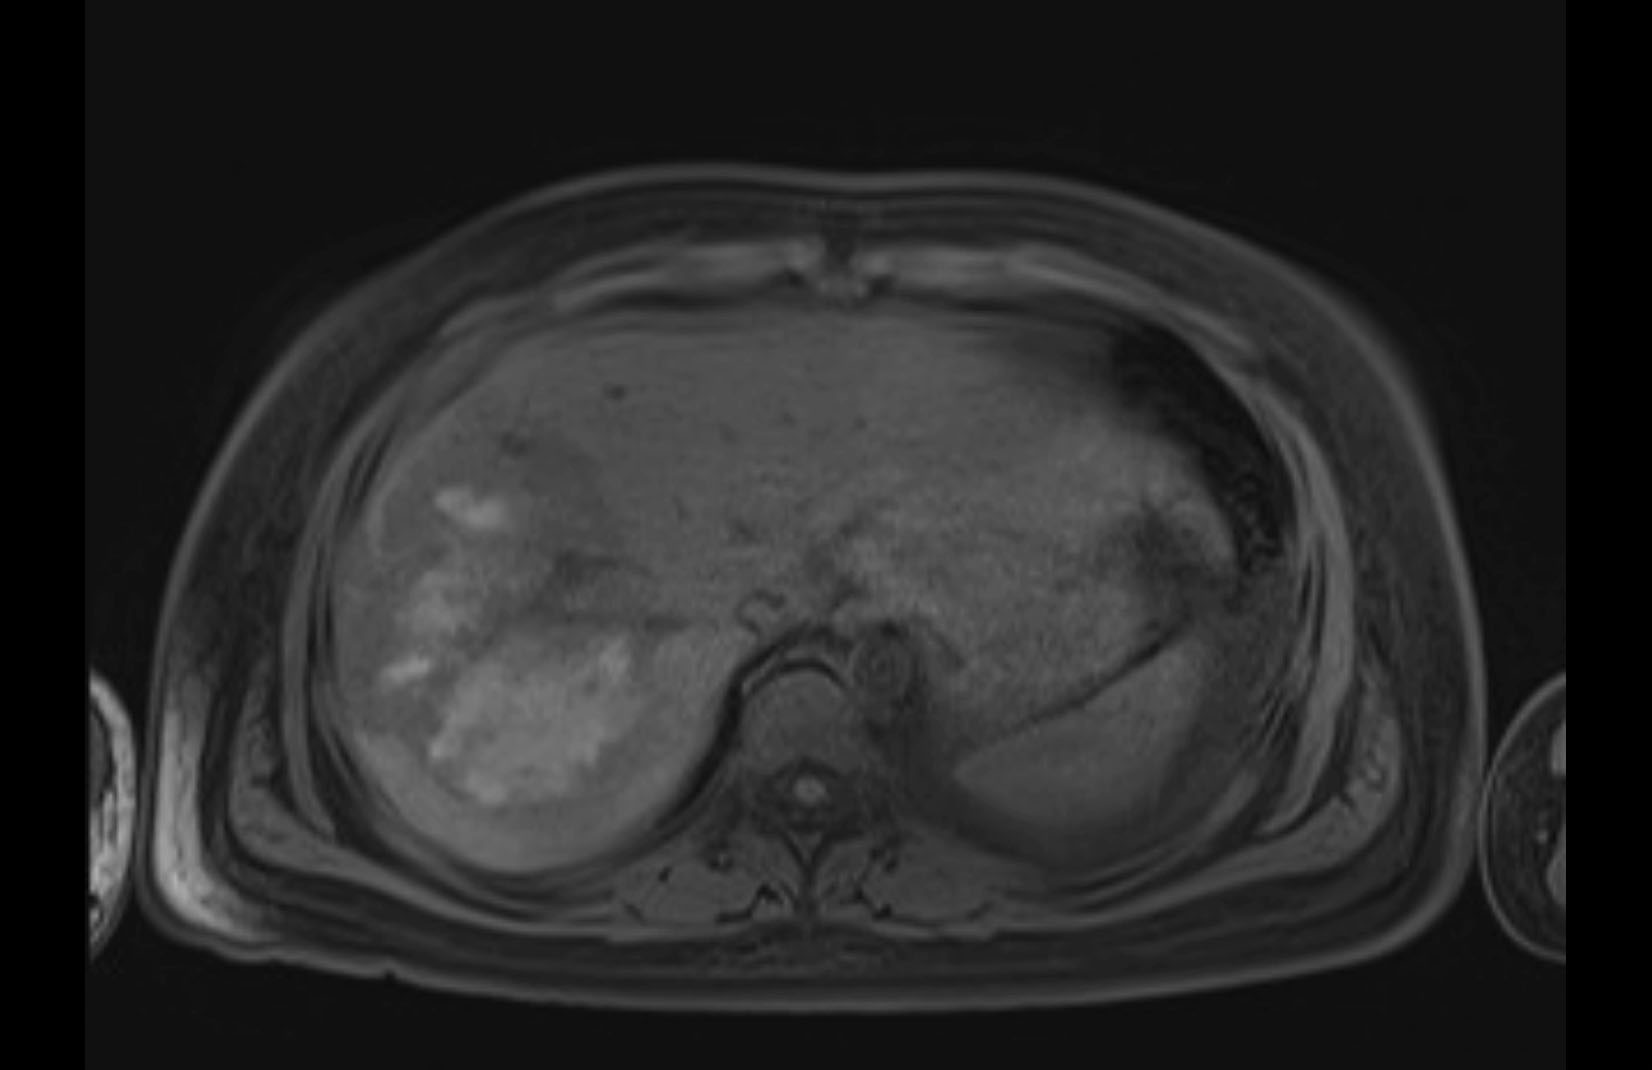

MRI T2

Imaging analysis

Based on initial findings, which issue(s) would you be most concerned about?